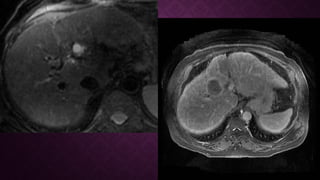

RESONANCIA MAGNETICARESONANCIA MAGNETICA

• T1 C + ( Eovist / Primovist )

• similar a la evaluación con Gd extracelular, pero la evaluación de la fase hepatobiliar

requiere atención.

• T2: variable, típicamente moderadamente hiperintensa

• C + post-SPIO (óxido de hierro): aumenta la sensibilidad en el diagnóstico de HCC

pequeños

• DWI: señal alta intratumoral; aumenta la sensibilidad y especificidad

RESONANCIA MAGNETICARESONANCIA MAGNETICA •T1 C + ( Eovist / Primovist ) • similar a la evaluación con Gd extracelular, pero la evaluación de la fase hepatobiliar requiere atención. • T2: variable, típicamente moderadamente hiperintensa • C + post-SPIO (óxido de hierro): aumenta la sensibilidad en el diagnóstico de HCC pequeños • DWI: señal alta intratumoral; aumenta la sensibilidad y especificidad